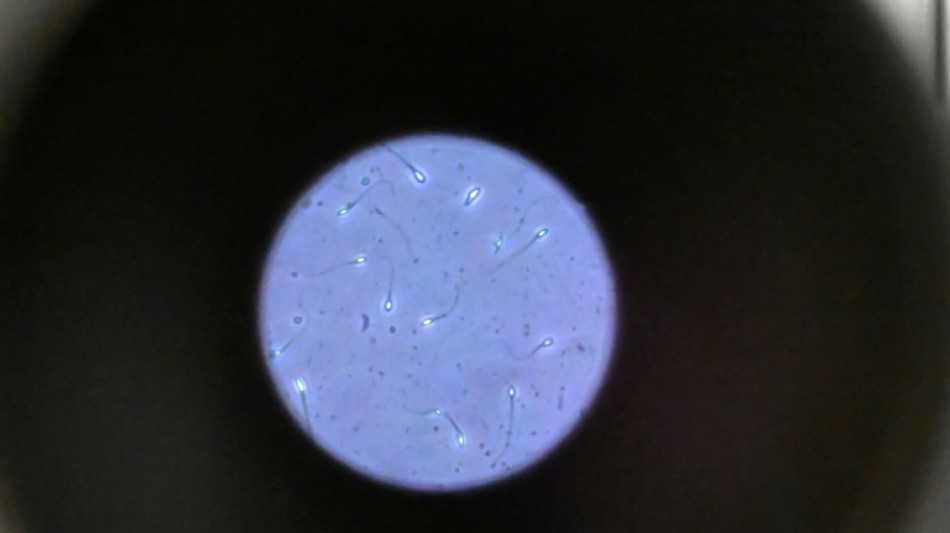

Dans l'espace, les spermatozoïdes ont du mal à trouver leur chemin / Photo: Damien MEYER - AFP/Archives

Dans l'espace, les spermatozoïdes ont du mal à trouver leur chemin vers l'ovule en raison de la microgravité, qui perturbe aussi le développement des embryons, selon une étude publiée jeudi dans Communications Biology.

Les chercheurs ont testé successivement du sperme de souris et humain dans ce dispositif placé dans un appareil en constante rotation pour simuler la microgravité.